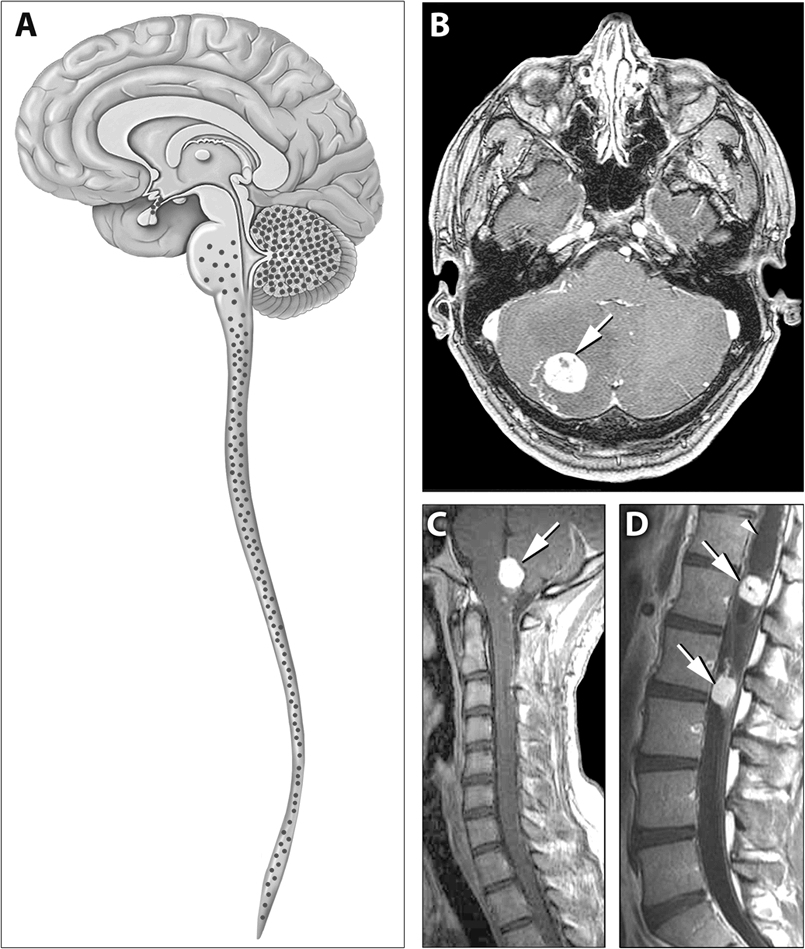

Het von Hippel-Lindau syndroom (angiomatosis cerebelli et retinae) is een zeldzame autosomaal dominant erfelijke aandoening (OMIM 193300) waarbij hemangioblastomen (capillaire haemangiomen) kunnen ontstaan in de retina, cerebellum en andere organen. Deze vaattumoren veroorzaken problemen door de groei in vitale structuren. Patiënten met een hemangioblastoom in het oog hebben vaak verminderd zicht of worden blind. Het netvlies kan loslaten. Bij een hemangioblastoom in de hersenen kan de druk in de hersenen toenemen, met als klachten hoofdpijn, dubbelzien, misselijkheid en braken, epileptische aanvallen, apathie, uitvalsverschijnselen.

Naast hemangio­blastomen van de retina (40-60%), cerebellum en myelum (55-60%) kunnen ook feochromocytomen (0-20%), niercelcarcinomen (20-40%), tumoren van de saccus endolymphaticus (binnenoor), neuro-endo­criene pancreastumoren (5-20%) en multipele cysten in de nieren, pancreas en epididymis of ligamentum latum uteri voorkomen. De tumoren ontstaan vaak al vanaf jonge leeftijd (24 jaar). De belangrijkste doodsoorzaak is een hemangioblastoom in het cerebellum (50%), gevolgd door niercelcarcinoom (35%). De diagnose van Hippel Lindau syndroom wordt gesteld bij aanwezighed van een hemangioblastoom in combinatie met een positieve familieanamnese, of bij 2 of meer hemangioblastomen (circa 20% de novo mutaties). De aanwezigheid van het VHL gen kan worden bevestigd met DNA-diagnostiek in Rotterdam en Utrecht. Patiënten die drager zijn moeten vanaf 5 jaar jaarlijks door de oogarts worden gezien. Vanaf 10 jaar jaarlijks lichamelijk onderzoek inclusief screening op metanefrines in bloed of urine. Vanaf 15 jaar tweejaarlijks MRI schedel. Echo bovenbuik op indicatie.

Illustratie: Wikimedia (Creative Commons License)